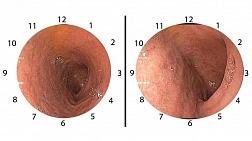

- Классификации

- Атлас